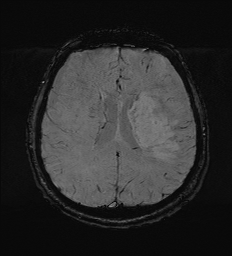

| DWI | ADC |

![]() |

| DWI (Diffusion-Weighted) | Restricted water diffusion (acute stroke, abscess) | Normal brain tissue, vasogenic edema | Hyperacute stroke โก, abscess vs cyst, encephalitis |

| ADC Map | Normal diffusion (bright) | Restricted diffusion (dark in stroke) | Confirms true restriction (differentiate stroke vs T2 shine-through) |